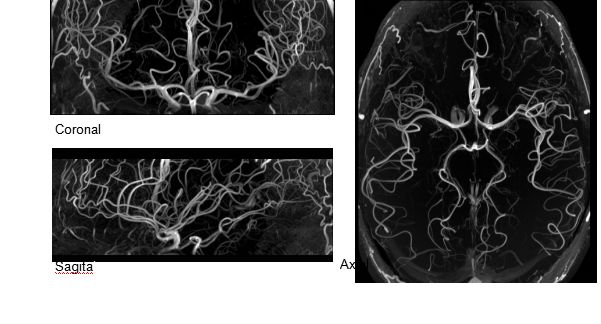

(TOF)300微米的各向同性分辨率顯示最小的血管